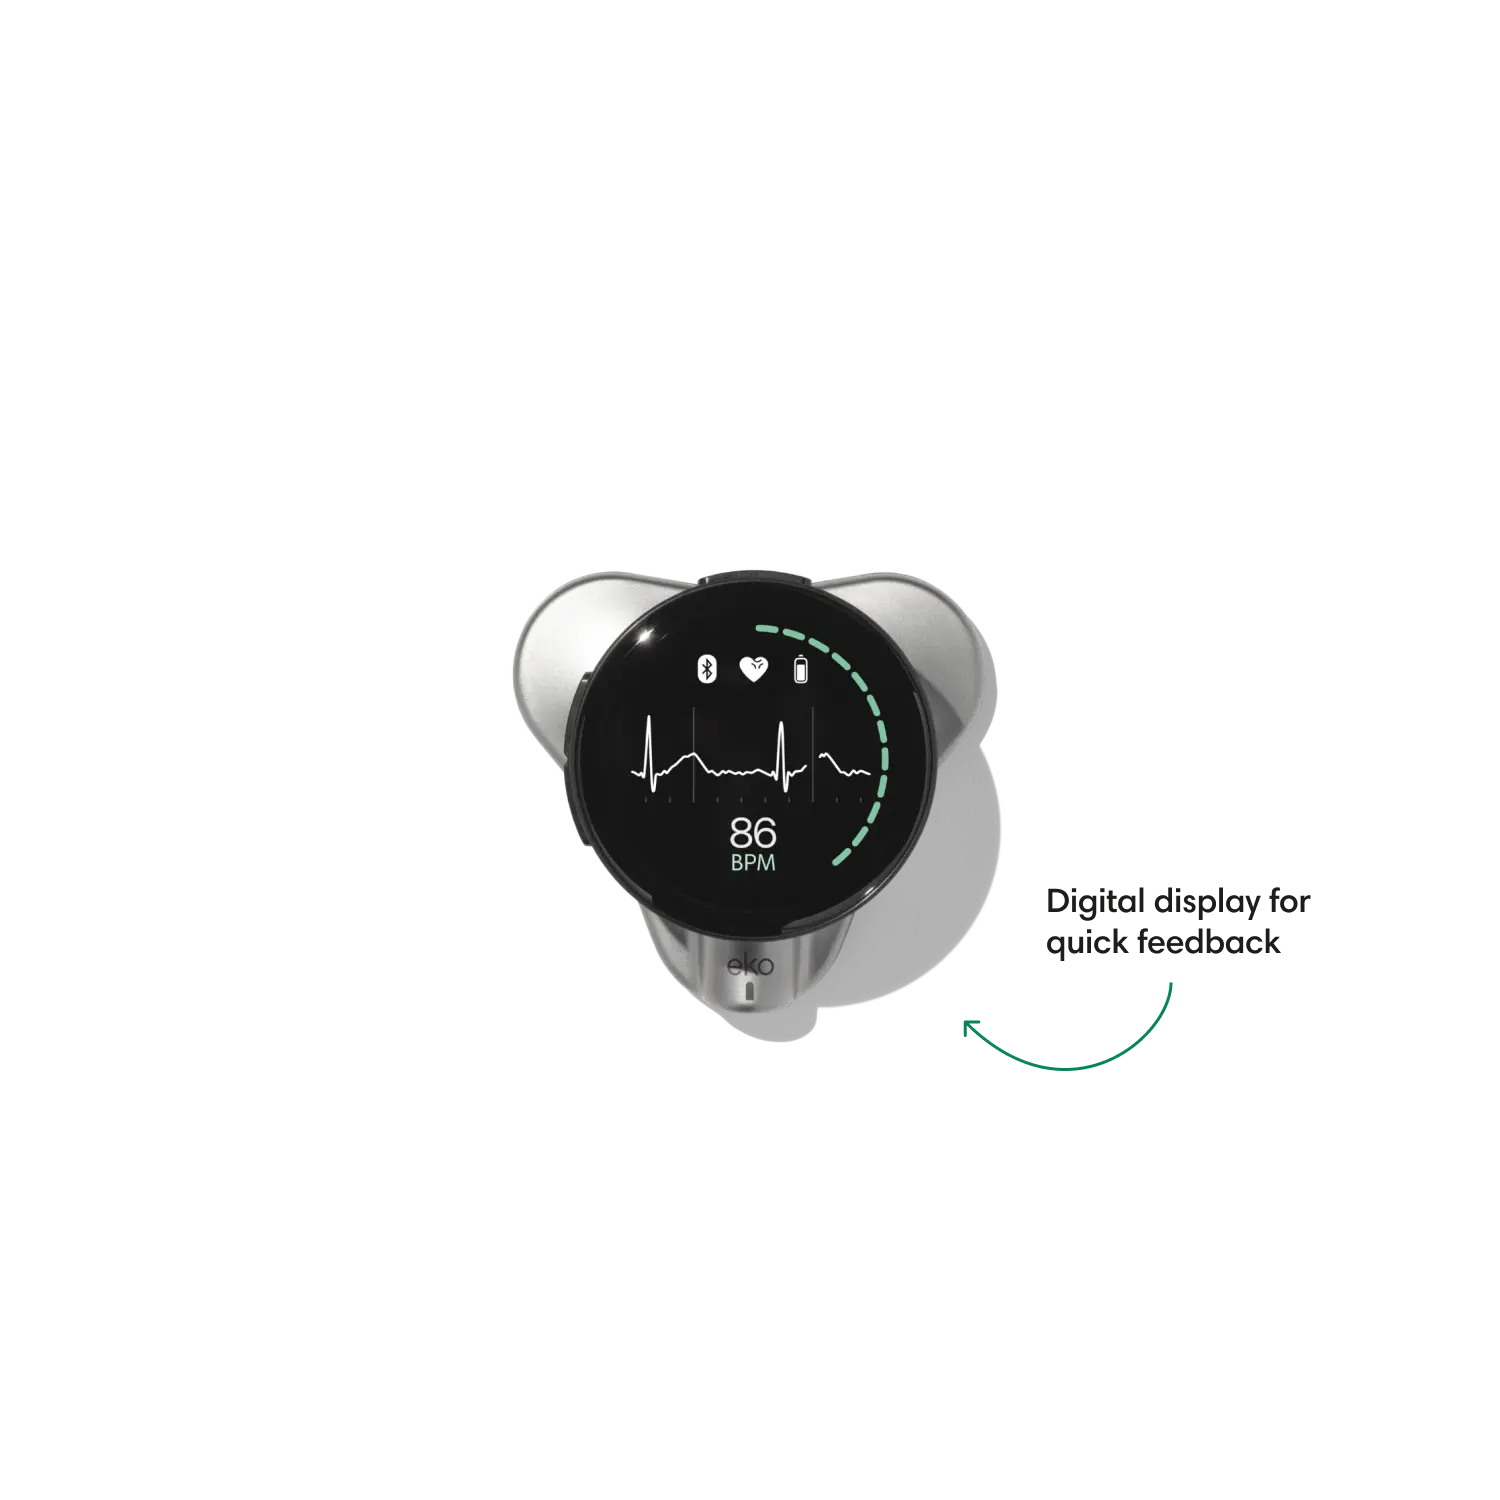

Go beyond sound alone.

For the first time ever, measure heart rate, visualize 3-lead ECG, and see detection results — right on a built-in, full-color display.